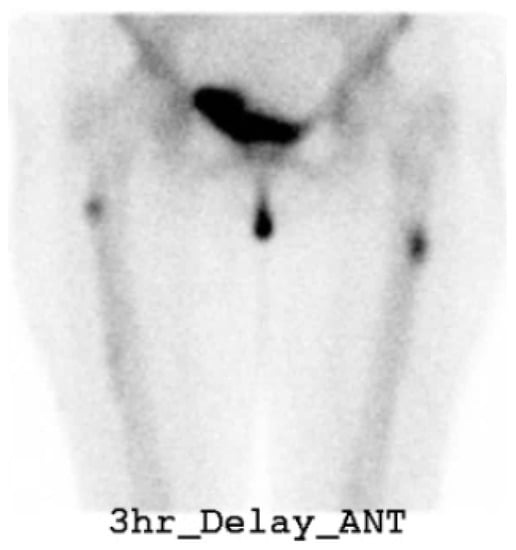

- Kim, J.E.; Yun, M.; Lim, S.-K.; Rhee, Y. Concurrent bisphosphonate-related bilateral atypical subtrochanteric fractures and osteonecrosis of the jaw on bone scintigraphy. Clin. Nucl. Med. 2015, 40, 450–452. [Google Scholar] [CrossRef]